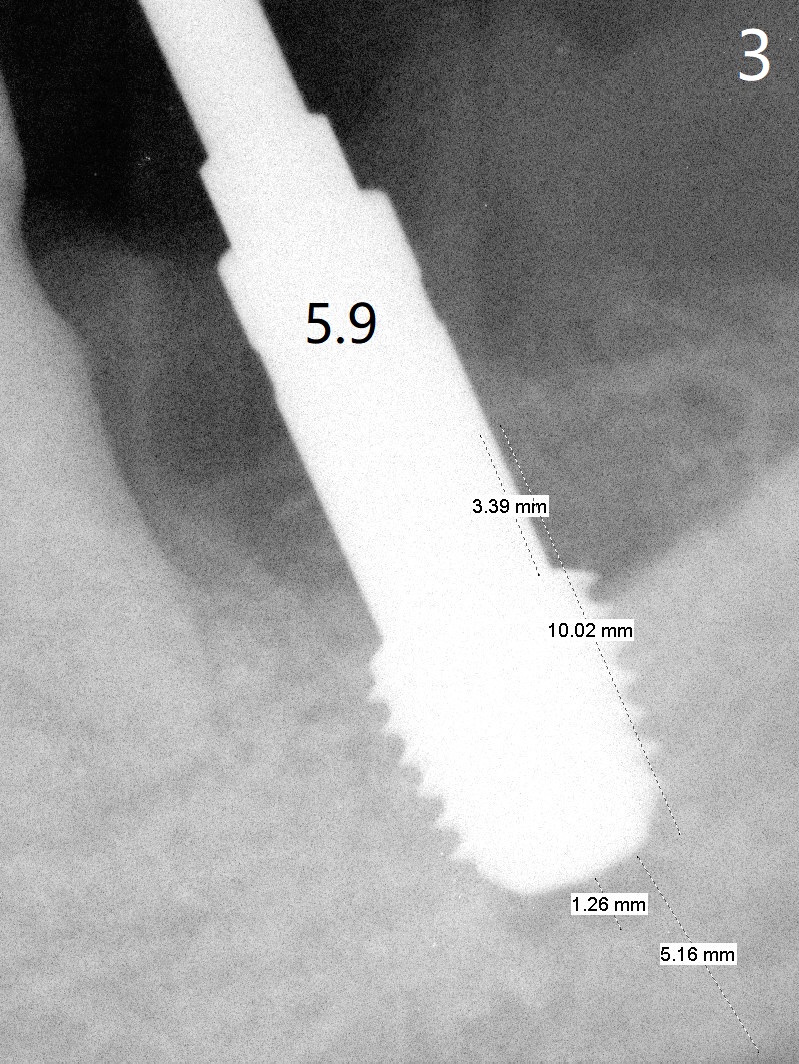

After extraction, curettage and Clindamycine gauzes in the sockets of the tooth #18 for 3 times, a 2 mm pilot drill makes initial osteotomy in the socket from 8 to 14 mm (Fig.1 (gingival level)). It appears that the osteotomy should move distal (Fig.1: red line, Fig.2 (17 mm)). After 5.9x10 mm drill, a 5.9 mm tap is placed (Fig.3). There is 4 mm clearance. Following 6.4x10 mm drill for 2 mm deeper, a 6.4x10 mm implant is placed with 60 Ncm. The implant plateau is level with the lingual crest, while the mesiobuccodistal bone is low. Autogenous bone mixed with Osteogen is placed in the defect area, followed by insertion of a 6.8x4(4) mm abutment (Fig.5). Collagen dressing is placed on the top of the graft. An immediate provisional is fabricated to close the remaining socket. Impression is taken 7 months postop (Fig.6). There seems to be no bone loss 23 months post cementation without opposing teeth (Fig.7) in spite of severe periodontitis at #19 (Fig.8 (25 months post cementation)). More surprising is the asymptomatic lingual (L) plate perforation, revealed by CT (Fig.9 arrowheads).